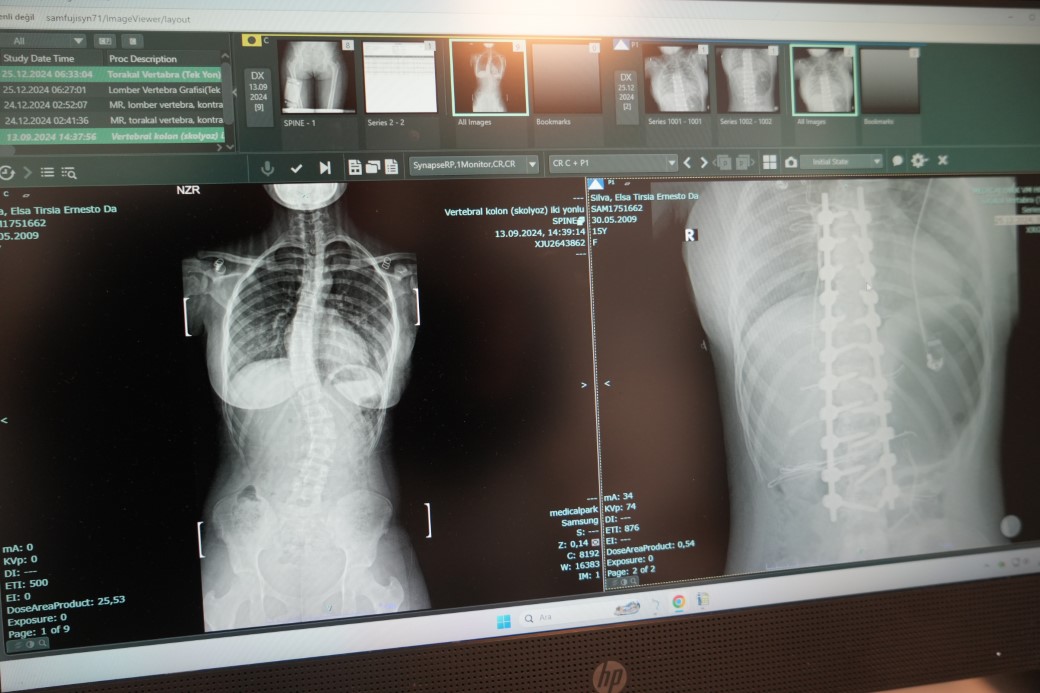

Afrikalı Elsa, omurgasındaki 45 derece eğrilikten Samsun’da kurtuldu

Angola’dan Samsun’a şifa bulmak için gelen skolyoz hastası 15 yaşındaki Elsa Silva’ya VM Medical Park Samsun Hastanesi’nde skolyoz ameliyatı yapıldı. Yapılan ameliyat ile şiddetli ağrılarından ve bel eğriliğinde kurtulan Elsa Silva, çok mutlu olduğunu söyledi.

Hastanın ameliyatını gerçekleştiren Ortopedi ve Travmatoloji Uzm. Prof. Dr. Turgut Nedim Karaismailoğlu, "Hastamızda skolyoz mevcuttu. 2 ay önce bize geldi. Angola’da yaşıyorlar. Geldiğinde 45 derece bel eğriliği mevcuttu. Yaşı 15’ti ve bu yaşta ameliyat olması gerekiyordu. Hasta, ameliyattan sonra ikinci gün ayağa kaldırıldı. Üçüncü günde taburcu edildi. 15. günde dikişleri alındı. Bu ameliyatlar ağır ve dikkat isteyen ameliyatlardır. Bu konuda Türkiye’de son dönemde çalışan uzman sayısı arttı. Samsun’da bu imkan olduğu için çevre ülkelerden gelen hasta sayısında artış mevcut. Biz de onlara elimizden geldiğince cevap vermeye çalışıyoruz" dedi.